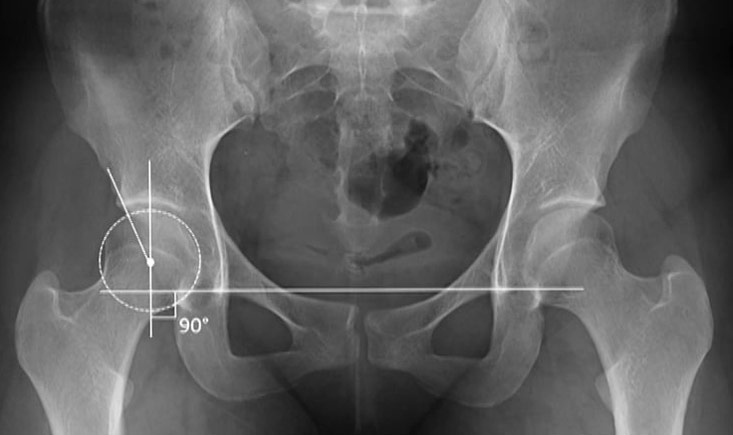

In this session on the evolving landscape of hip arthroplasty, the first presentation explores whether resurfacing might be a superior option for younger patients compared to THA. The second presentation provides a comprehensive consensus on managing hip and groin pain among physically active adults, offering evidence-based guidelines. Finally, the last presentation examines the potential risks and challenges associated with custom-made hip implants, emphasizing the importance of careful consideration in their use.